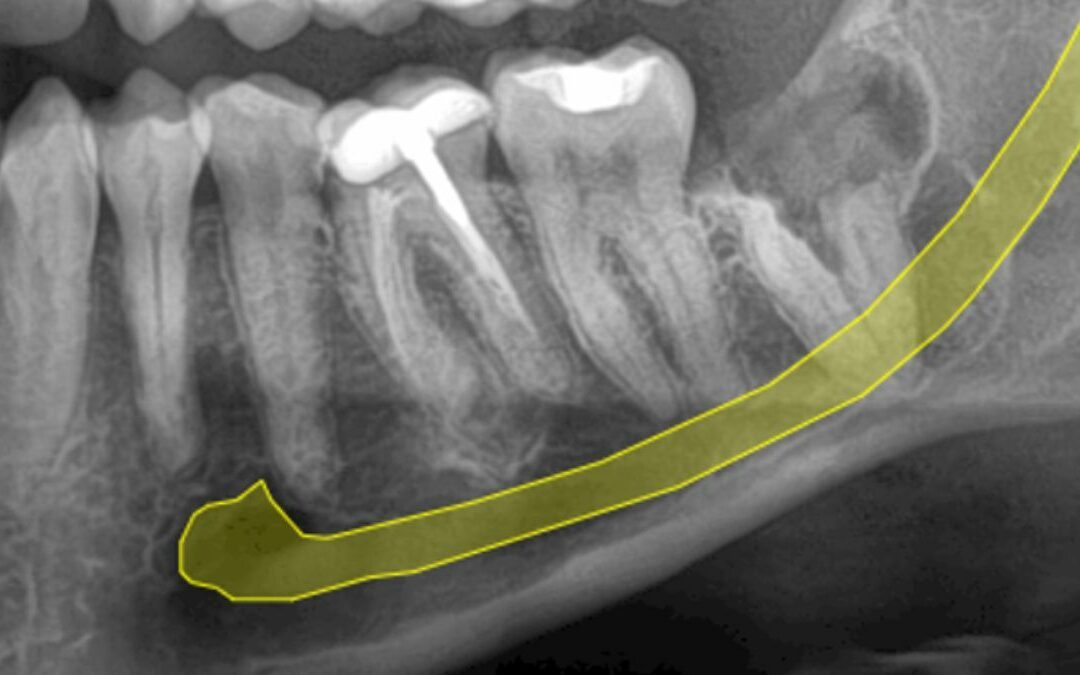

Es importante una vez realizada la técnica, realizar seguimiento al paciente porque en algunos casos se puede evidenciar el desplazamiento de la raíces hacia la boca y realizar la extracción de las raíces sin tener riesgo de afectar el nervio,

En DENTARÓ realizamos un control exhaustivos a todos nuestros pacientes, aquí les dejamos un caso realizado por el Dr. José Daniel Márquez Gámez, de un año de evolución donde fue necesario realizar la extracción de las raíces sin afectar el nervio en ningún momento.

Tomografía computarizada de control postoperatorio al año, se evidencia desplazamiento de las raíces, sin relación con el nervio alveolar.